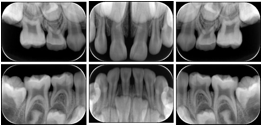

Intra-oral radiography typically involves acquisition of multiple images of various parts of the dentition. Many digital radiographic systems offer customized templates that are used for displaying the images in a study on the screen. These templates may also be referred to as mounts or view sets. The Structured Display Object represents a standard method of encoding and exchanging the layout and intended display of Structured Displays. A structured display object created in this manner could be stored with a study and exchanged with images to allow for complete reproduction of the original exam.

1. A patient visits a General Dentist where a Full Mouth Series Exam with 18 images is acquired. The dentist observes severe bone loss and refers the patient to a Periodontist. The 18 images from the Full Mouth Series along with a Structured Display are copied to a DICOM Interchange CD and sent with the patient to see the specialist. The Periodontist uses the CD to open the exam in his Dental Radiographic Software and consults via phone with the General Dentist. Both are able to observe the same exam showing the images on each user's display using the exact same layout.

Intra-oral Full Mouth Series Structured Display

Figure OO-1. Intra-oral Full Mouth Series Structured Display